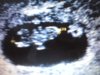

Przedstawiam wam nasze szczęście

Sorki za jakość ale komórka robiłam podczas badania wiec szału nie ma

Zobacz załącznik 675219